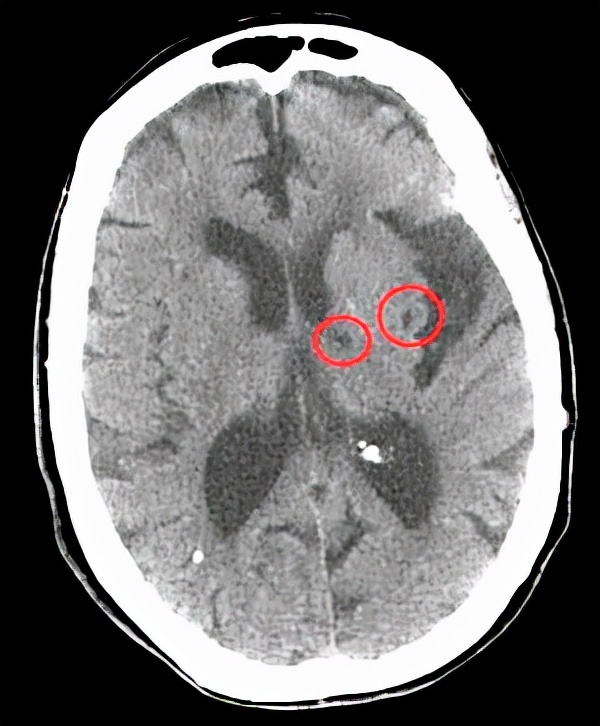

一、脉络丛钙化。

在报告单上经常可以看到脉络丛钙化这个名词,很多人一看:脑子里面有钙化了,一定是不好的东西。

真是这样吗?其实并不用害怕,脉络丛钙化可能并没有什么问题,只是你的大脑血管有些老化而已。

而随着年龄的增长脉络丛可能出现钙化,通常都是生理性的,并不需要太在意。

另外也要看具体情况,有没有其他的症状体征,如果什么问题都没有,一般是不需要处理的,也不需要用药。

但是如果有症状呢,身体真的感觉不一样了,脉络丛钙化可能也预示着某些肿瘤的出现,甚至和脑积水也相关,这个时候就不要轻易放过了。